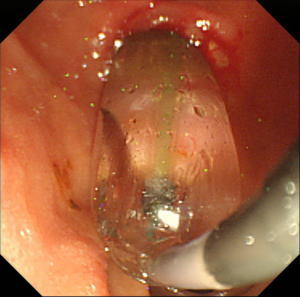

【EPLBD】 |

乳頭拡張後に採石用のバスケット(金属線の器具)を用いて結石を破砕することなく除去しました。 |

除去した結石です。この方法では結石を破砕しなくて済むため、1回の処置でほぼすべての結石を除去することができます。 |